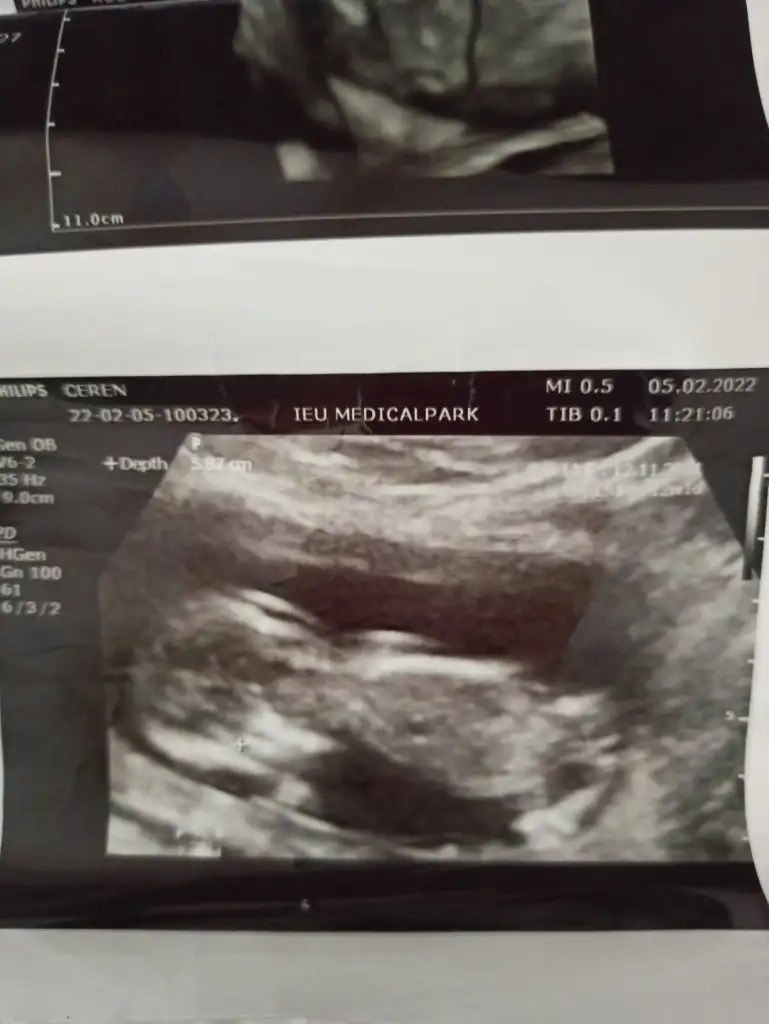

ozele gidiyorum aslında kizlarda 12. haftdada bende öğrenmiştim kesin konusmuslardi o zaman usg var ekliyorum yorumlarsanız sevinirim en azından kafam rahatlasin istiyorum ikilemde kalmak kötü hissediyor

Renkli usg ye doktor bisey demedi mi bacaklarını toplamış gibi tam anlaşılmıyor

bacak arası hep sim siyah renkli olanda da bulanık anlayamadık doktorda o yuzden emin olamadı. sanırım daha bekletmek istiyor biraz daha merak edin diyor 😀hayırlısı nasılsa oyle olsun inşallah sağlıkla hayırla dogsunlar bütün bebekler